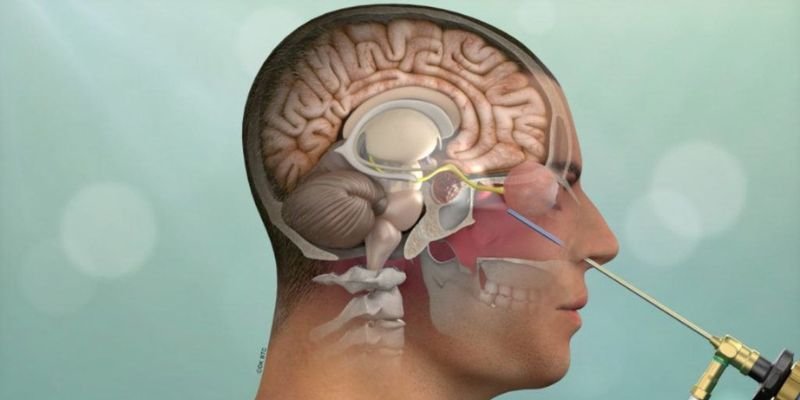

Brain Surgery

Advanced brain surgery ensuring precision, safety, and faster recovery through minimally invasive neurosurgical techniques.